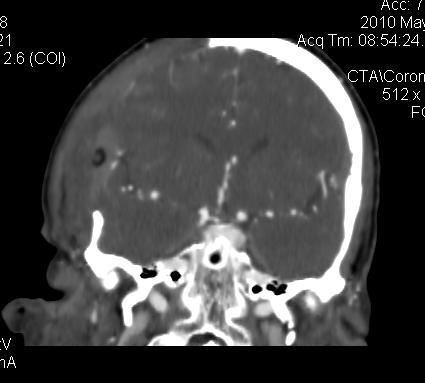

男.60岁,渐进性意识不清,ct检查双侧额颞顶部硬膜下血肿,开颅术后行脑血管cta,大脑中动脉起始部见一瘤状血管扩张。请各位老师留下宝贵意见

太常见了,报动脉瘤就可以

符合动脉瘤表现。

符合动脉瘤表现。

动脉瘤。

颅内动脉瘤。

后重建做得不是很好看,要将维蒂斯环充分显示,最好在增加一个mip。这样不好定位。

小动脉瘤

典型

符合动脉瘤的表现

动脉瘤

符合动脉瘤表现。

小动脉瘤

典型